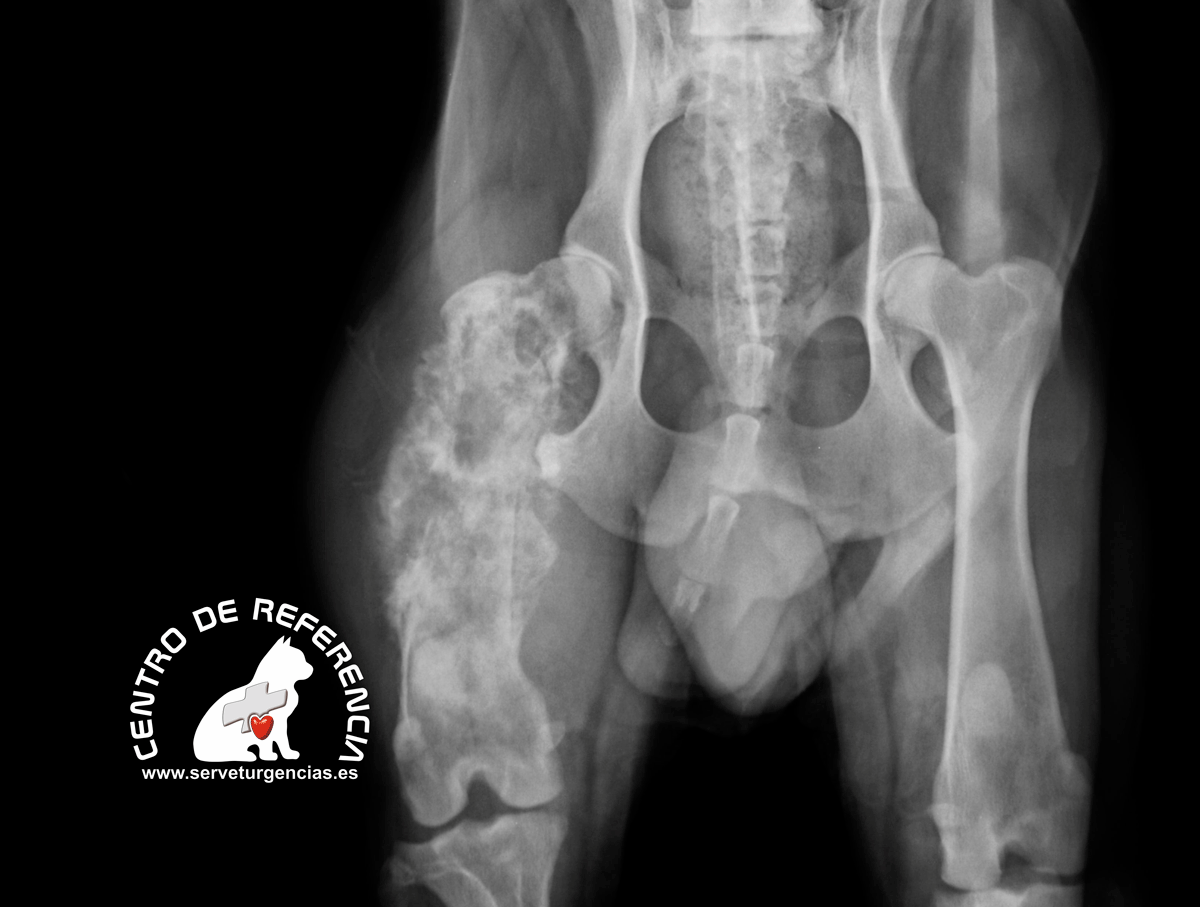

Radiografía característica de un tumor maligno de femur. pueden verse claramente áreas con lisis y esclerosis. El tumor eleva el periostio y se aprecia neoformación ósea. esto se corresponde con el Triángulo de Codman en el margen distal de la lesión. Este signo se asocia a malignidad pero también puede aparecer en osteomielitis.

Citograma y radiografía de un animal que padecía un osteosarcoma de femur.La primera imagen muestra un diagrama de puntos obtenido por citometría láser. Los monocitos se corresponden con el área verde de la gráfica.